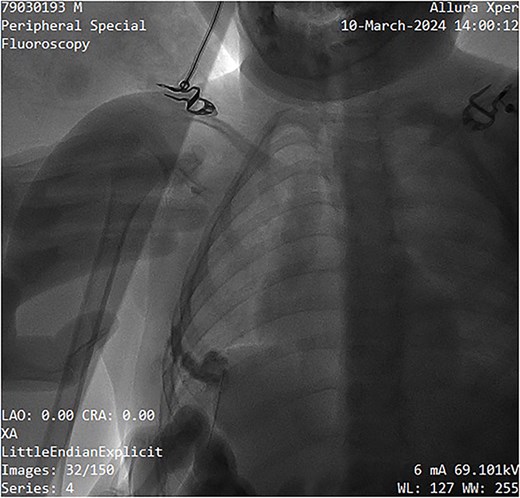

A single-needle direct-stick phlebography was performed using a 25-gauge butterfly cannula under ultrasound guidance. Blood aspiration confirmed the lesion's venous nature. Iopromide (Ultravist™) was administered and subsequent fluoroscopic imaging by Phillips Allura Xper FD System demonstrated slow contrast washout, further confirming the low-flow nature of the malformation (Fig. 3). Minimal venous drainage was observed, consistent with Puig Class I categorization [5].

Fluoroscopy image showing contrast administration into the malformation, confirming its slow-flow nature, and drainage pattern.